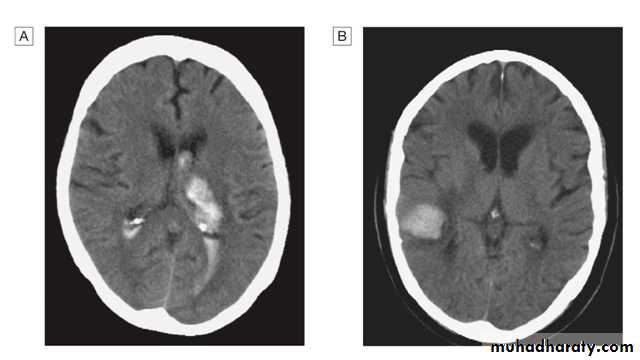

Of patients with a stroke, 85% will have a cerebral infarction and the remainder will have had an intracerebral haemorrhage.Brain imaging is required to distinguish these pathologies and to guide management.

Intracerebral hemorrhage

This usually results from rupture of a blood vessel within the brain parenchyma but may also occur in a patient with a subarachnoid hemorrhage if the artery ruptures into the subarachnoid space.

Hemorrhage frequently occurs into an area of brain infarction.

The haemorrhage itself may expand over the first minutes or hours, or it may be associated with a rim of cerebral oedema, which, along with the haematoma, acts like a mass lesion to cause progression of the neurological deficit. If big enough, this can cause shift of the intracranial contents, producing transtentorial coning and sometimes rapid death.

CT is the most practical and widely available method of imaging the brain. It will usually exclude non- stroke lesions, including subdural haematomas and brain tumours, and will demonstrate intracerebral haemorrhage within minutes of stroke onset However, especially within the first few hours after symptom onset, CT changes in cerebral infarction may be completely absent or only very subtle.

CT and MRI may reveal clues as to the nature of the arterial lesion. For example, there may be a small, deep lacunar infarct indicating small-vessel disease, or a more peripheral infarct suggesting an extracranial source of embolism.

In a haemorrhagic lesion, the location might indicate the presence of an underlying vascular malformation, saccular aneurysm or amyloid angiopathy